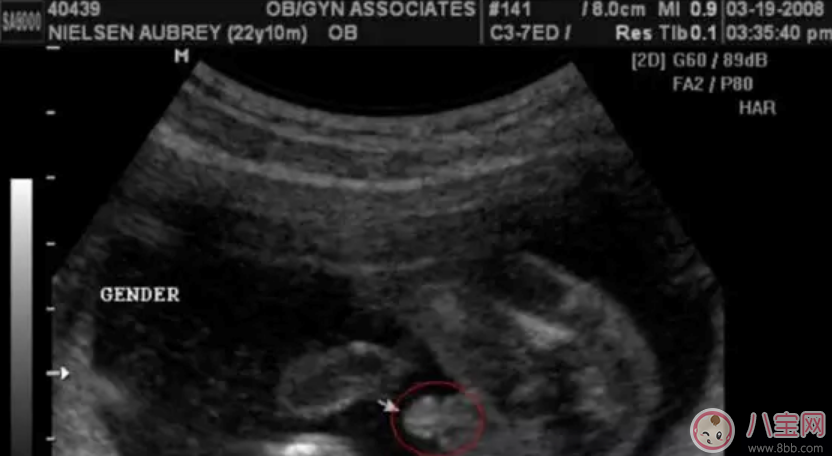

男寶寶四維彩超圖

"凸出的東西" 是他的標(biāo)記: 你們看到圓圓的是蛋蛋,如果看到圓圓的加小腸的就是全部JJ